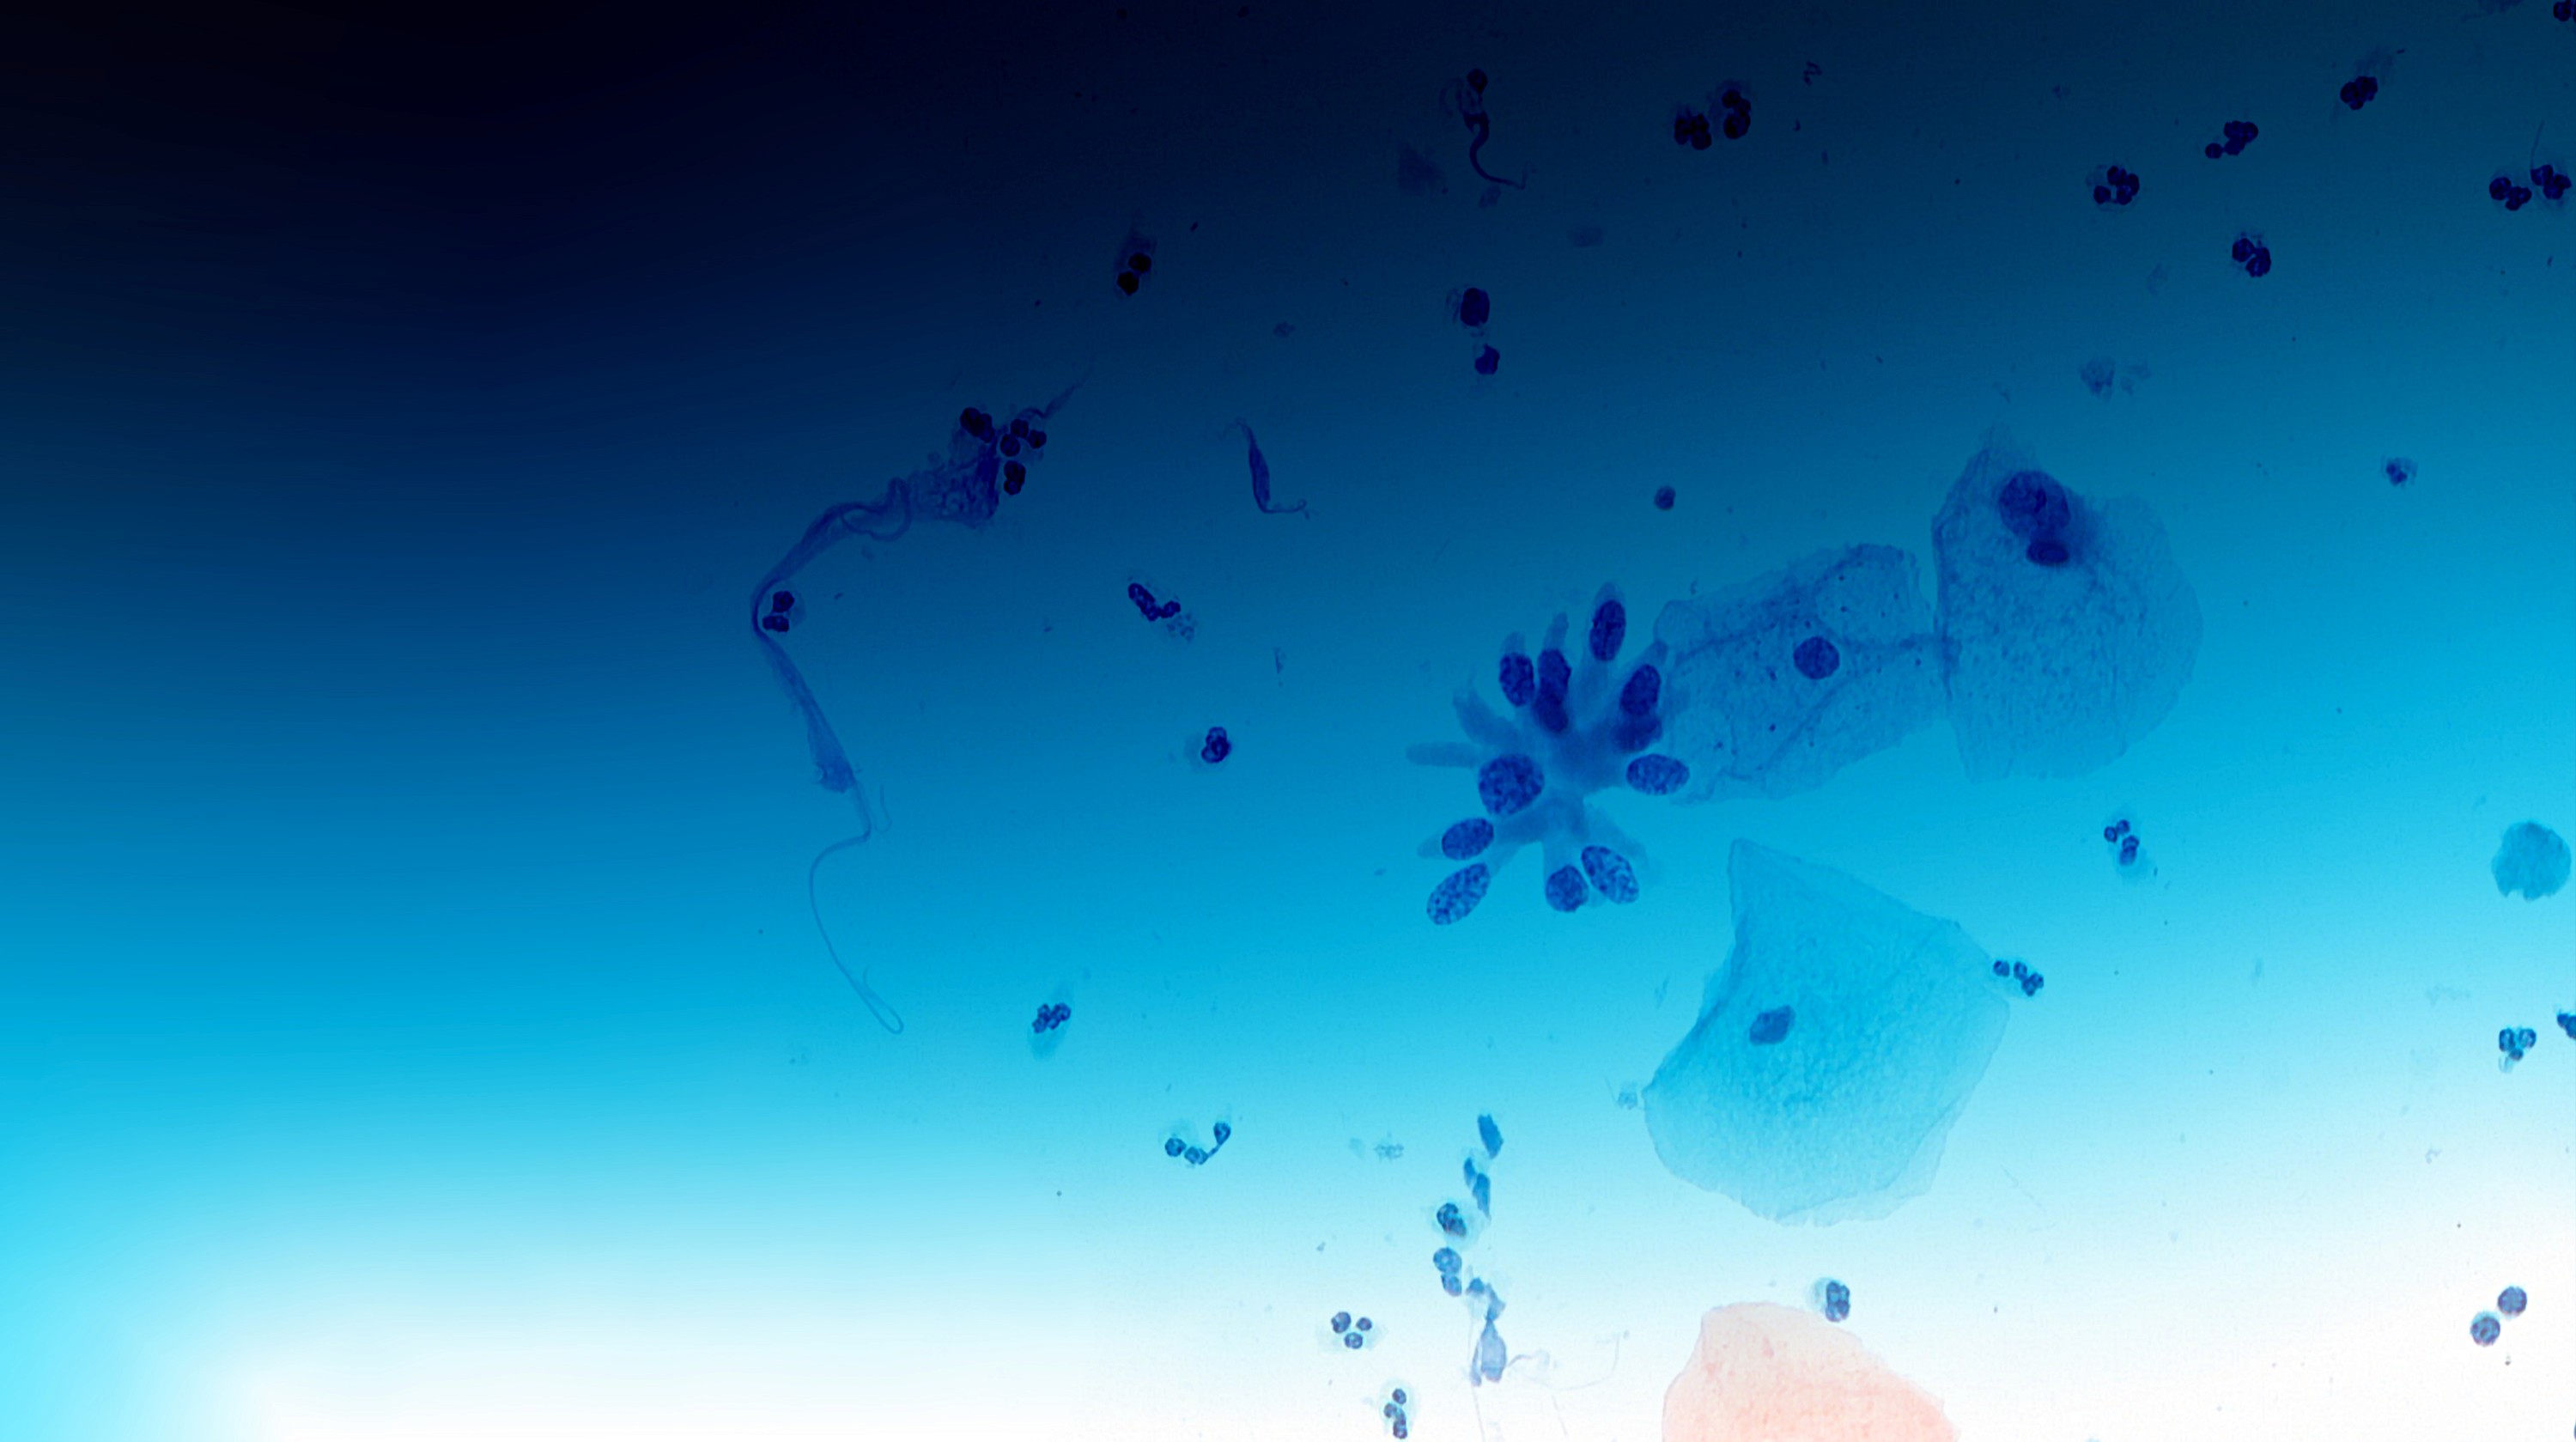

CytoProcessor® analyzes your slides seamlessly in the background as your scanner uploads the slide images. It identifies and locates potentially abnormal cells present on the digitized slides. The fully automated system leaves you free to work on other tasks. Cells are shown in a gallery, sorted from the most to the least diagnostically relevant. Each cell can be viewed in its context with the possibility of zooming in and out just like with the microscope.